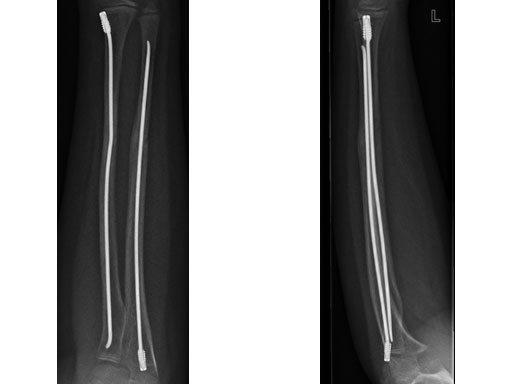

Case 2: Oblique forearm, shaft fracture (22D/5.1) with end caps, 11-year-old boy.

Case provided by Theddy Slongo, Bern, Switzerland